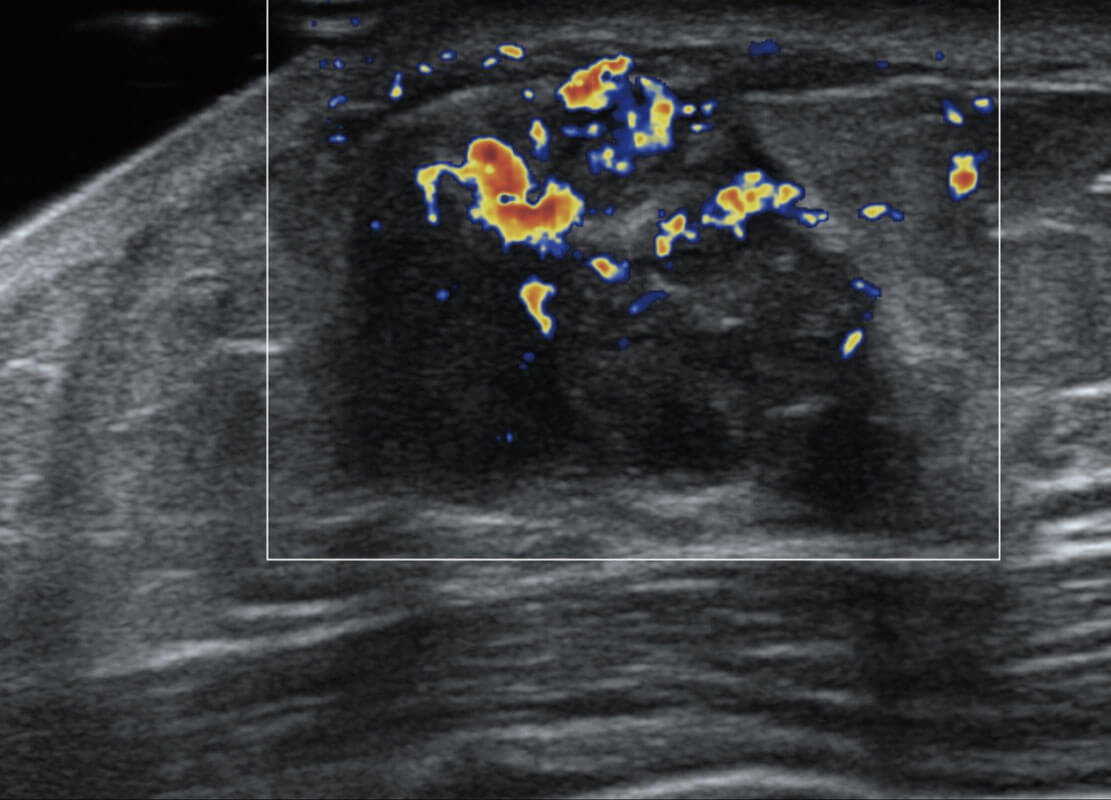

乳腺超声 / 新生儿

P60搭载宽频带线阵探头、宽景成像、弹性成像技术,为您提供乳腺应用方案。P60支持高频相控阵探头、线阵探头、腹部高频探头、腹部微凸探头等,丰富的探头群搭载敏感的彩色血流成像,适用于新生儿多种脏器检测要求,满足新生儿筛查需求。

• 新生儿肝血管癌